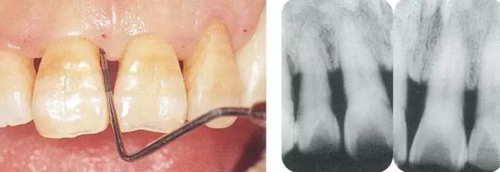

▼圖10-3(左)  進行浸潤麻醉后,在入刀前一定要用探針確認牙槽嵴頂?shù)奈恢茫╯ounding)。此時,要預(yù)測好手術(shù)刀的角度。

▼圖10-4(右)  進行Submarginal incision之前,首先做切線設(shè)計,之后將手術(shù)刀片朝著牙槽嵴頂做深切。